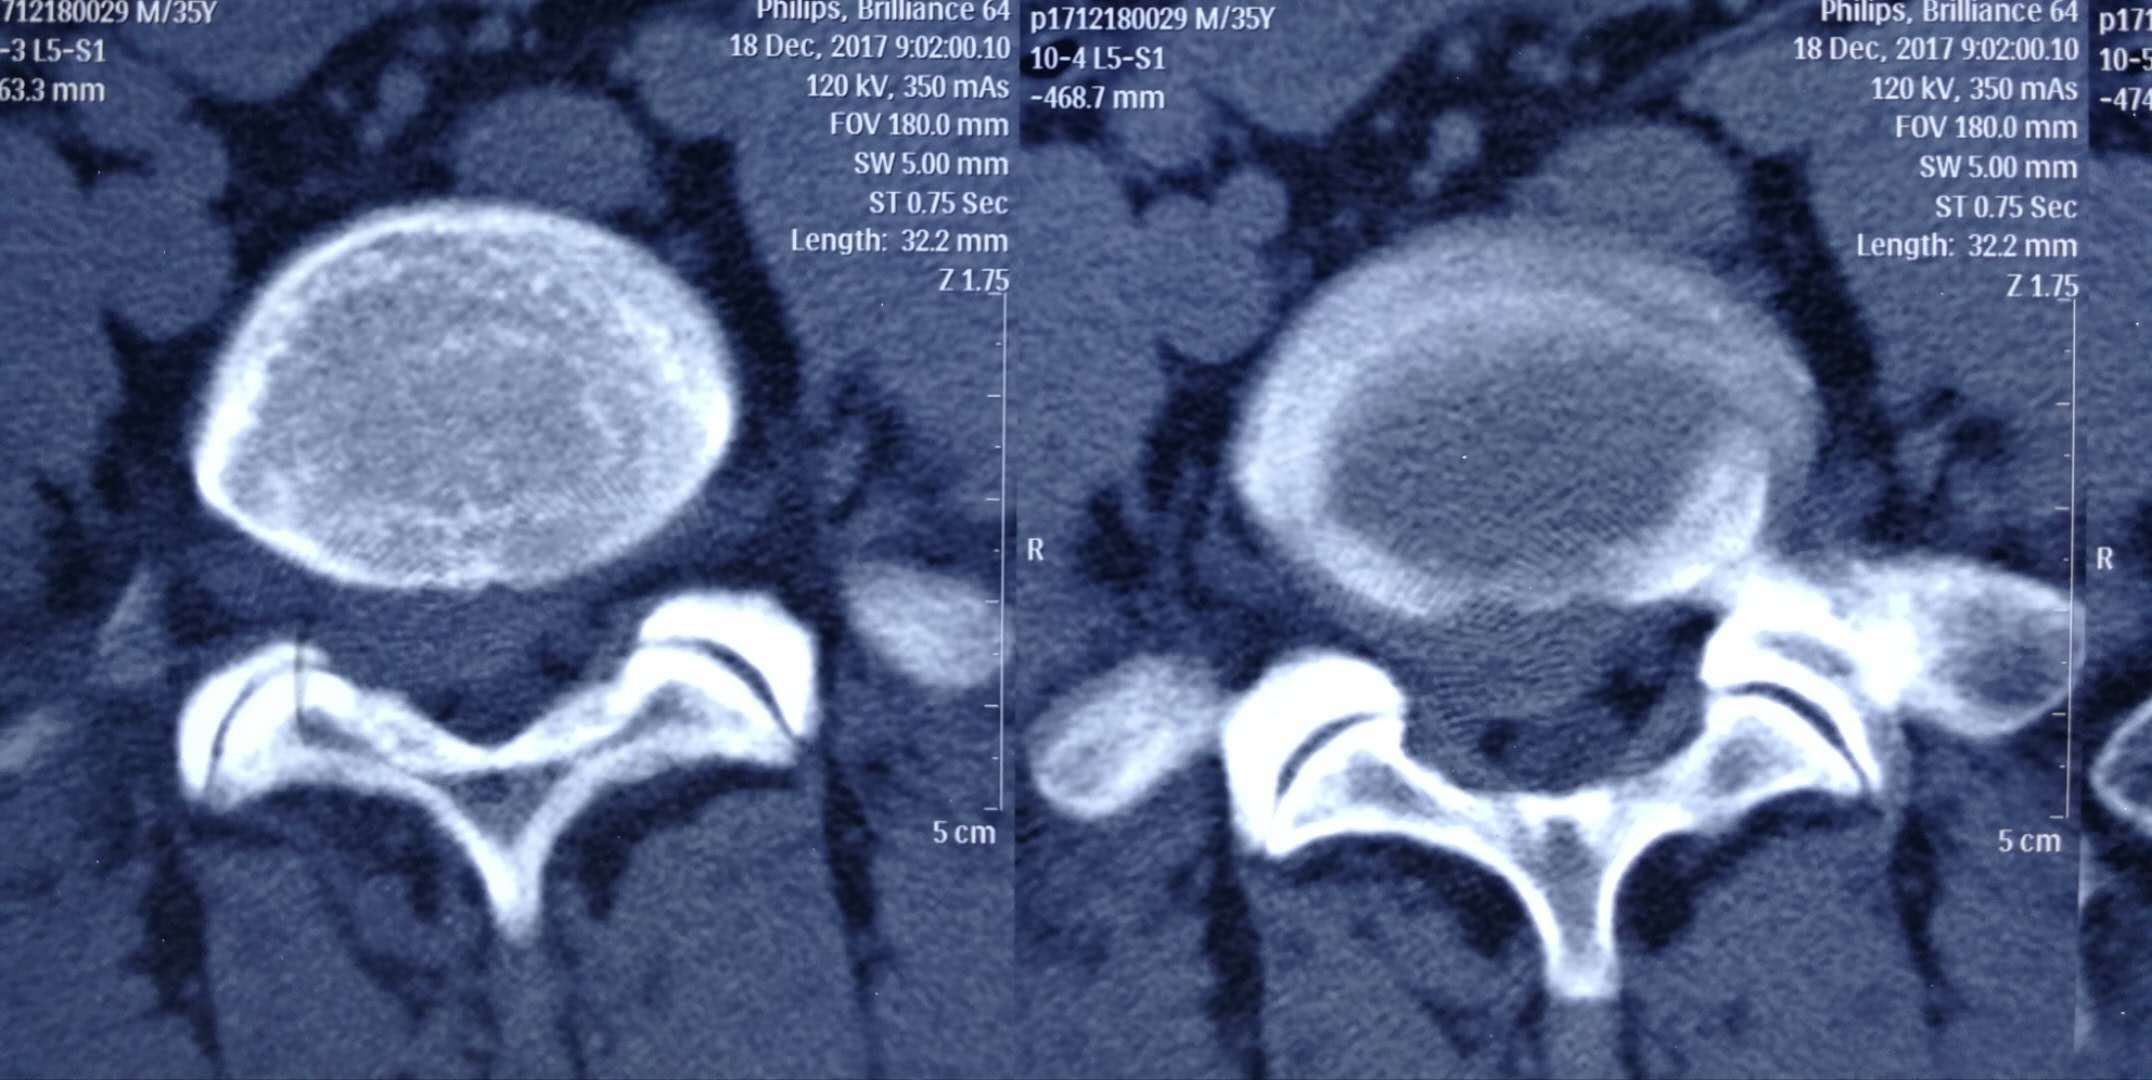

现在的CT/MR检查,能在检查完后就产生图像,再进行鼠标点拨间就可以完全显示全部图片。然而,有了图像并不一定就可以做出正确诊断。影像科医师还需要对图像进行再处理,以完整清晰地显示病变所在,再将图像传送到PACS(图像采集传输存储系统)服务器;同时,技师还要编辑排版将几十幅甚至上百幅图像打印成胶片,这些都需要时间。

诊断医生根据先后排列顺序,同时调阅参考患者的病史资料,仔细阅读观察分析患者影像学的每一幅图像,找出差异,鉴别真伪,寻找疾病的蛛丝马迹,做出一个初步的诊断意见。如果是复诊或者此次检查与以往病史相关,还要调阅以前的影像图片进行比对;有些临床病史不清的,还要亲自询问病人追加病史;有的复杂影像难以立即诊断,还需翻阅书籍,查一些参考资料,或者需要在第二天召集集体读片或专家会诊。

为提高影像诊断报告的正确性,对初级报告的审核复诊显得相当重要。一般医院都由高年资主治医师以上的医生或科主任担任审核复诊工作。通过上级医生的再次阅读、比对、修改等审核过程,最后打印成正式报告,才算完成一个病例的诊断过程。但CT、MR检查报告,因所涉及的检查过程较复杂,图像数量多,出诊断报告所需时间相对较长。目前,一般医院对外承诺CT检查2小时后、MRI检查半天以后取报告,这样的时间安排是一个有利于医患双方的方案。